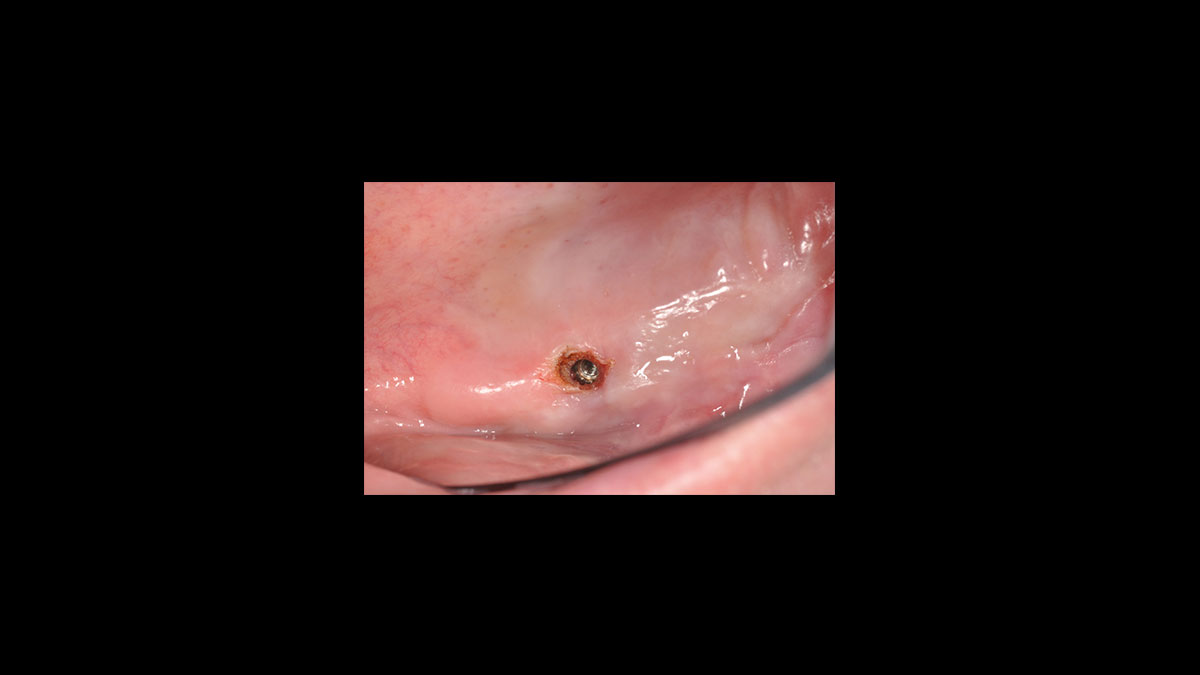

• Descubrimiento del implante

Descubrimiento del implante